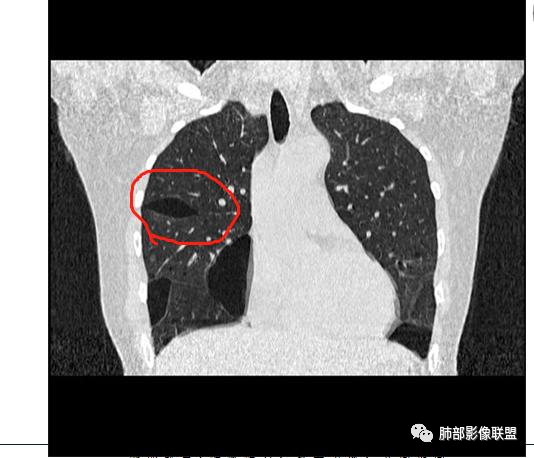

青年女性,ct双肺多发囊性病变,形态不规则,左肺舌段,肋隔角受累,下叶多,母亲有类似病史,考虑BHD,鉴别LAM。

年轻女性,双肺多发囊性病变,双下肺多,大囊为主,考虑为BHD可能,查下皮肤及肾脏。

青年女性,双肺多发囊性病变,形态不规则,下叶多且大,母亲有类似病史,考虑BHD。多发肺大泡+肾脏肿瘤+皮肤纤维囊腺瘤=BHD

双肺多发大小不等肺气囊,边界清楚,薄壁,壁光滑,以胸膜下分布为主,肋膈角也有受累,临床年轻女性,考虑LAM(年轻女性好发),鉴别BHD(需要询问家族史),LCH(吸烟,及肋膈角不受累)。

双下肺为主多发怪异囊,与胸膜关系密切。青年女性,可疑家族史。考虑BHD。建议皮肤+肾脏检查。确诊:基因检测。

青年女性,两肺多发薄壁囊肿影,两下肺明显,母亲类似病史,考虑BHD,LAM

中年女性,双肺薄壁囊腔,肋膈角受累,考虑lam,鉴别BHD有家族史,复发性气胸,肾脏及皮肤病变。

青年女性,双肺胸膜下多发大小不等、多形态囊腔,薄壁,有肺大泡家族史,考虑BHD,鉴别LAM,建议结合肾脏、皮肤检查

年轻女性,无基础疾病,双肺胸膜下多发大小不等薄壁囊腔,壁光整,双下肺为主,肋膈角受累,无结节,无GGO,考虑LAM

青年女性,双肺胸膜下多发大小不等、多形态囊腔,肺大疱,有肺大泡家族史,考虑BHD,鉴别LAM,建议基因检测

小叶中心,胸膜下囊,比较大,规则:

这个图好,下次我们就这样的不是叶间胸膜,而是胸膜下囊

Birt-Hogg-Dubé综合征:影像符合,家族史符合

BHD主要影像表现特征:    1、两肺内肺囊肿:80%以上的BHD患者会出现肺内囊肿,且倾向于基底部近胸膜下分布,特别是纵膈侧肺膜下,囊肿形状不规则、囊肿可大可小,肺内囊肿多毗邻肺下动脉或静脉近端,胸部CT上囊肿分布和特点对诊断有提示意义。    2、继发自发性气胸:BHD患者发生气胸风险是正常人的5倍,BHD患者的气胸发生率约为 1/4,气胸复发率则高达59%。   3、肾肿瘤:(常为双侧性、倾向于嫌色细胞组织学亚型)   4、皮肤表现(为面、颈部纤维性毛囊瘤、毛盘瘤)